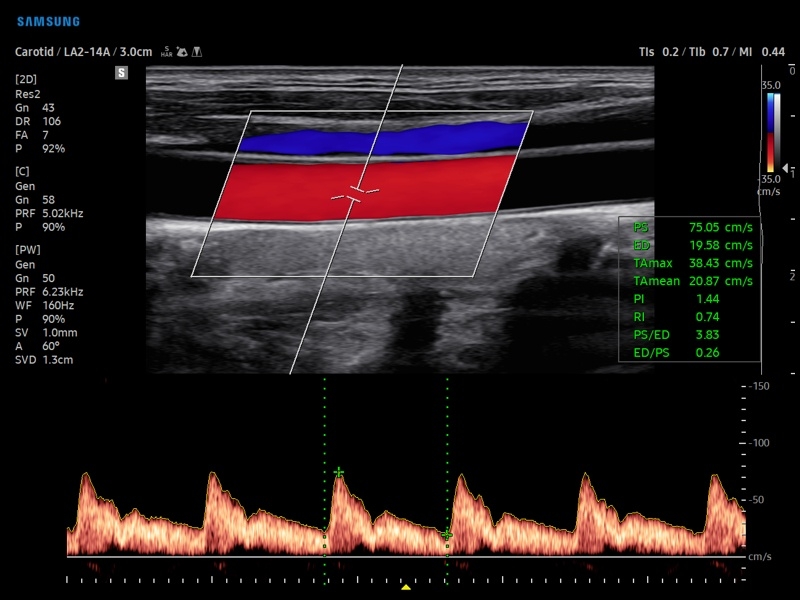

• Расширенная сосудистая визуализация: Auto IMT+, 2D Arterial Analysis

• Модуль AutoIMT - автоматическое вычисление комплекса интима-медиа общей сонной артерии (Intima Media Thickness). Данная оценка имеет большое значение для ранней диагностики атеросклероза и оценки риска развития инсульта и инфаркта миокарда.

• Модуль 2D Arterial Analysis программа, позволяющая автоматически провести анализ толщины и эластичности стенок разных участков сонной артерии, с выведением результатов в графической форме в движении (кинопетле) аналогично программе Strain для эхокардиографии.

• Сонные артерии:автоматическая, полуавтоматическая, ручная трассировка доплеровского спектра; ПСС, КДС, %СтПлощ, %Ст Диам, площадь сосуда, диаметр сосуда, средняя толщина интимы, объемный кровоток.